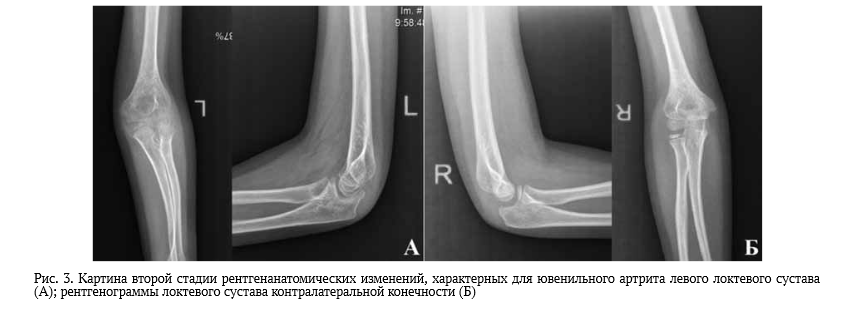

Отрицательная динамика рентгенологической картины на первой стадии, как правило, заключалась в визуализации признаков ускоренного роста (гипертрофии) головки мыщелка и блока плечевой кости, локтевого отростка локтевой кости и головки лучевой кости с начальными проекционными (неистинными) признаками сужения суставной щели и явлениями склерозирования субхондральных зон суставных поверхностей (рис. 3.)

Выявление признаков деформации в виде характерной неровности или зазубренности субхондрального контура суставной поверхности блоковидной вырезки локтевого отростка локтевой кости или головки луча в области лучелоктевого сочленения у детей свидетельствовали о начале или активном процессе формирования эрозивного компонента и прогрессировании заболевания (II стадия анатомических изменений). Рентгенологические признаки ускоренной оссификации хрящевых моделей и ее неравномерная асимметрия в эпифизах, образующих сустав, выглядели более наглядными у детей младшего возраста в дебюте и периоде разгара заболевания. Следует обратить внимание, что данного рода изменения при ЮИА должны наблюдаться во всех структурах, образующих сустав, подверженных артритическому процессу различной степени выраженности, без исключения.